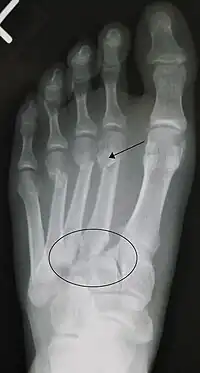

![]() Fractura de lisfranc, marcada con el círculo. Además, fractura a nivel distal del 2º (marcada con una flecha), 3º y 4º metatarsianos. | ||

El diagnóstico se basa en la imagenología y la clínica, esta última se puede presentar con las características clásicas de una fractura (dolor, aumento de volumen e impotencia funcional) en la región media del pie, sumada a una equimosis en la región del arco plantar. La valoración radiográfica de las relaciones normales del complejo tarsometatarsiano se lleva a cabo en las proyecciones Dorsoplantar en la que la cortical medial de la cuña intermedia, se continua con la cortical medial de la base del 2º metatarsiano. En la proyección oblicua lateral: la cortical medial del cuboides se continua con la cortical medial de la base del 4º metatarsiano en las placas simples y de estrés.